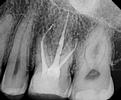

Our Vienna, VA dentists plan treatment using a digital x-ray image of the tooth. We may also recommend a 3-D digital scan of the tooth using CT cone beam technology. This valuable technology provides more information than a two-dimensional x-ray and allows for more precise treatment planning.

When we begin your root canal treatment, we first open a small hole in your tooth to access the root canal. Dr. Sanati and Dr. Sharahm use leading-edge rotary endodontic technology to gently and quickly remove the infected material. Instead of the manual steel files dentists used in the past, rotary endodontics employs an electrically-powered instrument that allows us to perform more efficient and comfortable root canals with a higher success rate for our patients.

When our Tysons dentists have cleared away every trace of the infection, they fill the hollowed-out space with an inert material called gutta-percha and then seal the tooth. Since there is no more blood supplying the tooth, it will become brittle, so we may recommend a dental crown to protect it. If you don't need a dental crown, we will still need to place a filling on the tooth to restore and strengthen it.